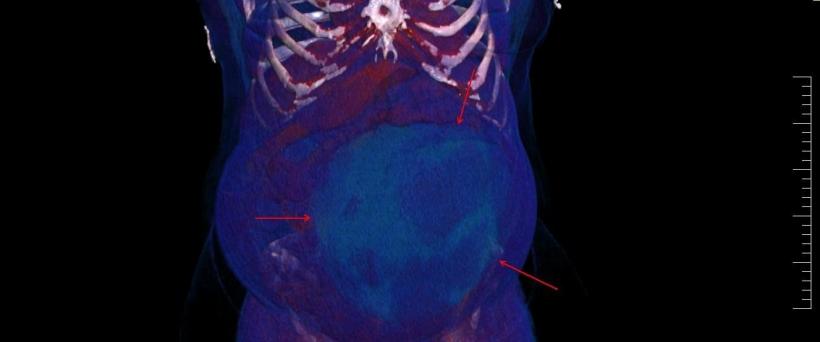

Performanță medicală la Sibiu: Chist ovarian de 4,5 kilograme, extirpat cu succes de la o pacientă | Galerie Foto | Imagine 3

Spitalul Militar de Urgență „Dr. Alexandru Augustin” Sibiu